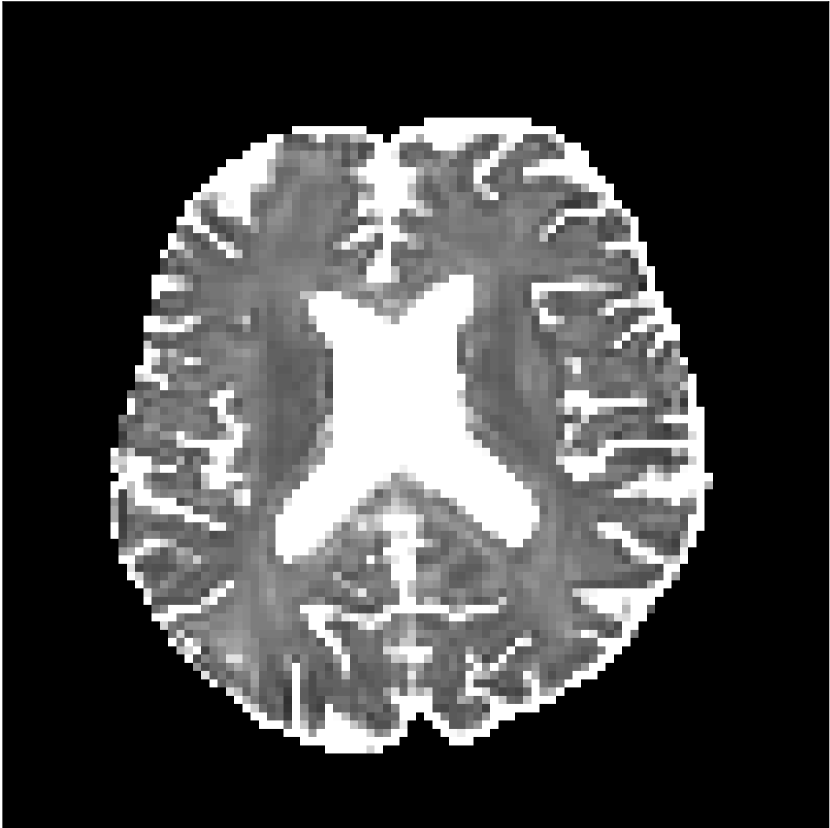

Figure 10 compares mean diffusivity maps across various partial Fourier factors between the CCNN and state-of-the-art methods.

No PF

7/8 PF

6/8 PF

5/8 PF

SoA

MD, m2/ms

CCNN

The methods perform similarly without partial Fourier acceleration, but as partial Fourier acceleration increases, the image is continually degraded in the SoA method, with "black voxels" appearing around the lateral ventricles. The CCNN method mitigates the appearance of these artifacts in the parameter maps.